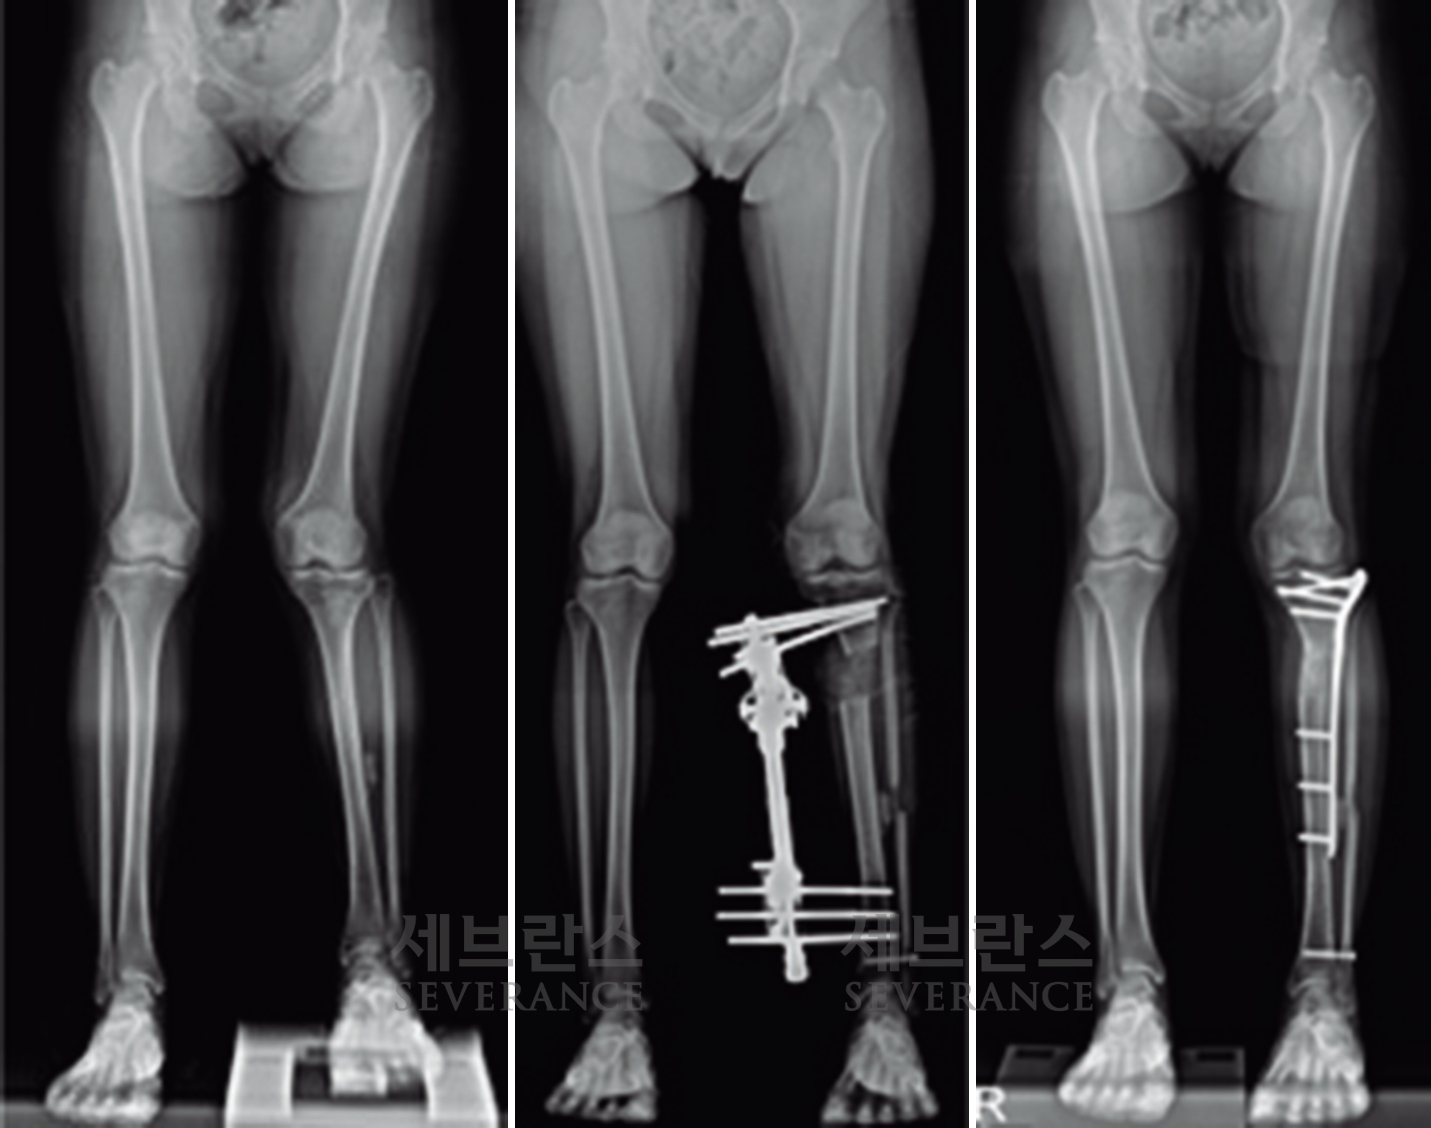

• 골연장술

양쪽 팔다리의 길이 차이가 큰 경우에 주로 시행하는 수술로, 외부 고정 장치나 내부 금속정을 이용해 뼈를 서서히 늘려 균형을 맞추는 방법입니다. 대체로 외부 고정 장치를 많이 사용하는데, 연장 기간 동안 날마다 정해진 횟수만큼 뼈를 조금씩 늘려야 하고, 핀 주변 소독도 꾸준히 해줘야 합니다. 연장된 뼈가 단단히 붙는 데도 수개월이 걸리기 때문에 환자와 보호자의 인내가 필요합니다.

성장판 손상으로 발생한 좌측 외반슬하지부동에 대해 골연장술과 교정술을 동시에 시행해 치료한 환아